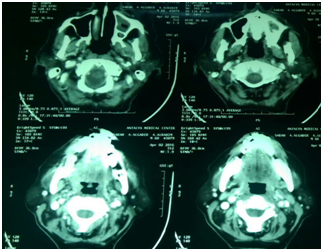

Over 60 year-old Sudanese woman knowledgeable with jaw problems initiate 12 months ago with spontaneous deep pain in the maxilla at the buccal left side. Her dentist referred her to the department of Oral Surgery, Khartoum Teaching Dental Hospital, when he identifies an extended exposed bone with pus discharge. The patient mentioned that over the 7 preceding months, she developed severe pain combined with episodes of swelling in the palate, discharge from bridge in left side of the upper jaw that extend from the upper central incisors to the first permanent molar in addition to halitosis.10 The past medical history she is adiabatic; had breast cancer and experience a wide local excision and auxiliary clearance 3 years ago. A six cycle chemotherapy regime was given since 2012. And 7 months ago bone scan confirmed skeletal metastasis in the vertebral column (Figure 1) and 12 cycle chemotherapy regime was given on 2016 (Zometa 4mg/month) intravenously.11 The intraoral examination revealed; marked halitosis, swelling in the palate which tender and discharge (blood + pus) on pressing, mobile bridge, mobility grade 3 in 26 and a large bony defect (yellowish exposed bone) in the upper left quadrant of the maxilla mainly involving the buccal alveolus under bridge (Figure 2). No extra oral findings were detected. Orthopantomogram view showed detected an osteolytic region in the maxilla left side (Figure 3) and C.T scan detected left maxillary mucosal thickening with nasal mucosal thickening (Figure 4). Incisional biopsy under local anesthesia was carried out with a segment of palatal mucosa adjacent to the necrotic bone.12 The pathology report showed only (mucositis) inflammation with no evidence of ulceration or neoplasia. Ciprofloxacin 500mg was prescribed for one month together with Chlorhexidine mouth wash. An isolation of the sequestrum, with mobility of the 26 tooth was obtained. It was decided to remove the left maxillary first molar and sequestrum conservatively.

Figure 4 Shows Axial cut of C.T scan.